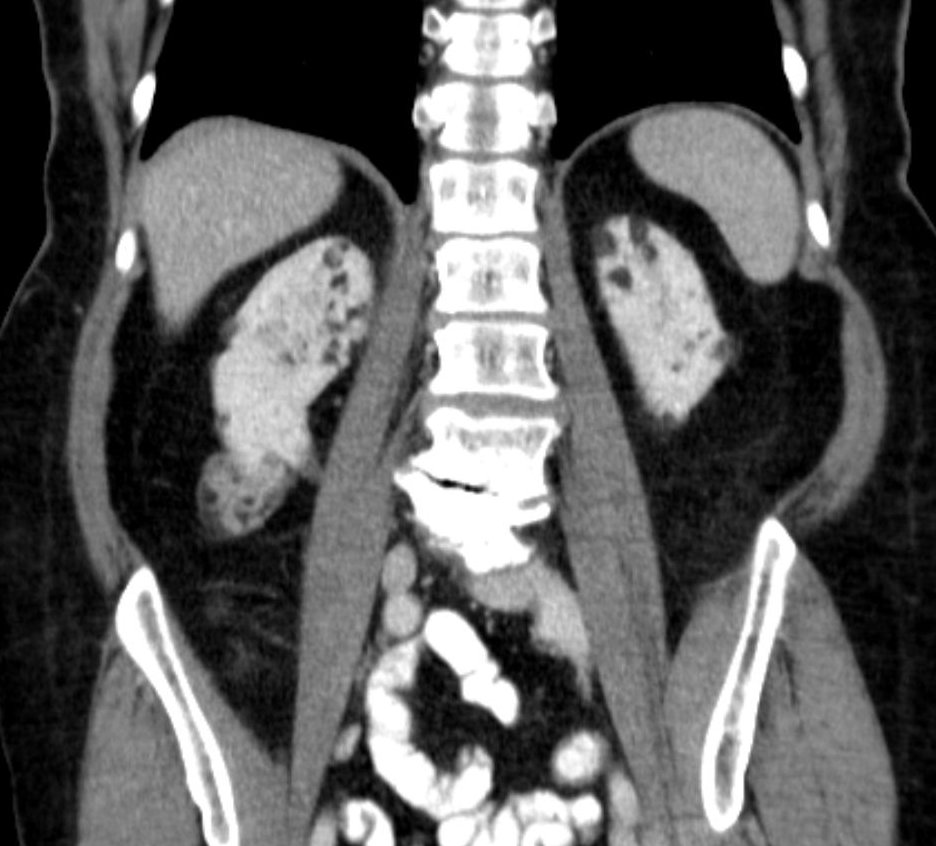

4. 3. 신장 증상

결절성 경화증 환자의 26%에서 80%는 혈관근지방종이라고 불리는 신장의 양성 종양을 가지고 있으며, 혈뇨가 가장 흔한 증상이다.[6] 결절성 경화증 혈관근지방종은 발병 연령(31.5세 vs 53.6세), 평균 종양 크기(8.2cm vs 4.5cm), 수술적 중재가 필요한 사례의 비율(50% vs 28%)에서 결절성 경화증이 아닌 혈관근지방종과 다르다.[6] 양성 종양이지만 4cm보다 큰 혈관근지방종은 자연적으로 또는 경미한 외상으로 잠재적으로 치명적인 출혈의 위험이 있다.

뇌 MRI를 통해 뇌 결절, 뇌실막하 결절, 뇌실막하 거대세포 별아교세포종 등을 확인할 수 있다.[21] 뇌파 검사(EEG)를 통해서는 뇌전증 여부를 확인하고, 발작 유형을 평가한다.[21] 복부 CT 또는 MRI를 통해 신장 혈관근지방종, 신장 낭종 등을 확인할 수 있다.[6] 고해상도 흉부 CT (HRCT)를 통해 폐 림프관평활근종증 여부를 확인할 수 있는데, 이는 주로 성인 여성에게서 나타난다.[7] 심장 초음파 검사를 통해서는 심장 횡문근종 여부를 확인할 수 있으며, 주로 영유아에게서 발견된다.[8] 안과 검진을 통해서는 망막 과오종 등을 확인할 수 있고[10], 피부과 진찰을 통해서는 피부 병변을 확인한다.[21]

결절성 경화증 환자의 26%에서 80%는 혈관근종이라고 불리는 신장의 양성 종양을 가지고 있으며, 혈뇨가 가장 흔한 증상이다.[6] 결절성 경화증 혈관근종은 발병 연령(31.5세 vs 53.6세), 평균 종양 크기(8.2cm vs 4.5cm), 수술적 중재가 필요한 사례의 비율(50% vs 28%)에서 결절성 경화증이 아닌 혈관근종과 다르다.[6] 양성 종양이지만 4cm보다 큰 혈관근종은 자연적으로 또는 경미한 외상으로 잠재적으로 치명적인 출혈의 위험이 있다.

mTOR 억제제는 종양 크기를 줄이고 출혈 위험을 감소시킨다. 출혈이 있는 경우, 색전술을 통해 혈관을 막아 지혈한다. 신장 절제술은 가급적 피해야 한다. 양성 신장 종양(AML)에는 외과적 절제나 에베로리무스(상품명 아피니토르)를 사용한다.

- 복부 MRI를 통해 다양한 장기의 종양, 특히 신장의 혈관근종을 검사한다. 혈압을 측정하고 신장 기능을 검사한다.

- 평생 동안 1~3년마다 복부 MRI를 반복한다. 매년 신장 기능을 확인한다. 혈관근종 출혈이 있는 경우, 색전술과 코르티코스테로이드로 가장 잘 치료된다. 신장 제거(신절제술)는 피해야 한다. 3cm보다 크게 성장하는 무증상 혈관근종은 mTOR 억제제 약물로 가장 잘 치료된다. 영상 검사에서 발견된 기타 신장 합병증에는 다낭성 신장 질환 및 신세포암이 있다.